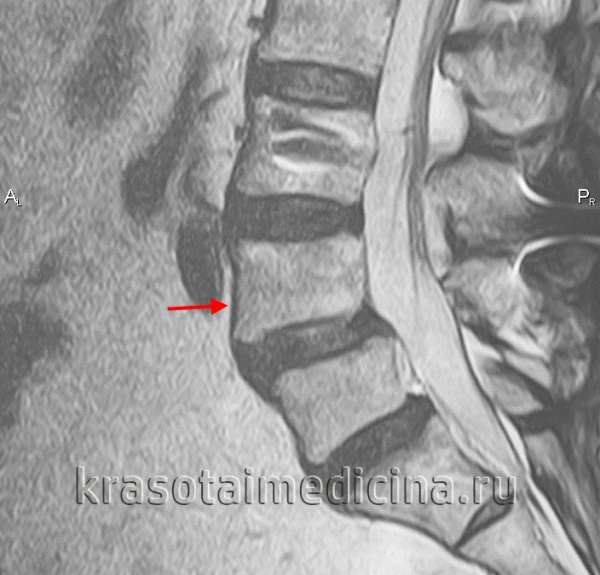

4. МРТ при спондилолизе:

• Т1-ВИ:

о Фокальное снижение интенсивности сигнала в области МЧ на сагиттальных и аксиальных изображениях

о Аналогичная картина на Т2-ВИ

• Т2-ВИ:

о Может отмечаться гиперинтенсивность сигнала в области МЧ и прилежащих участках костного мозга

• STIR:

о Отек костного мозга смежных с зоной дефекта участков и корня дуги

• Увеличение размеров спинномозгового канала

• Горизонтальная ориентация межпозвонкового отверстия на сагиттальных изображениях:

о Антеролистез

о Снижение высоты диска

о Исчезновение жировой клетчатки, окружающей расположенный в отверстии корешок

• Чувствительность МРТ: 57-86%

• Специфичность МРТ: 81 -82%

(Слева) Т1-ВИ, сагиттальная проекция: несвежий дефект межсуставной части дуги, характеризующийся нормальным сигналом жировой ткани костного мозга. На уровне L5-S1 видны признаки выраженного фораминального стеноза. Обратите внимание на нормальный низкоинтенсивный сигнал интактной межсуставной части дуги L4, зона которого может напоминать дефект.